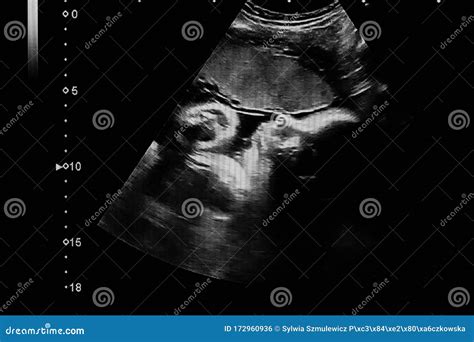

• Measure the baby's size and growth.

• Check the baby's position in the uterus.

• Assess the amount of amniotic fluid.

• Evaluate the placenta's position and health.

• Examine the baby's organs and systems for any abnormalities.